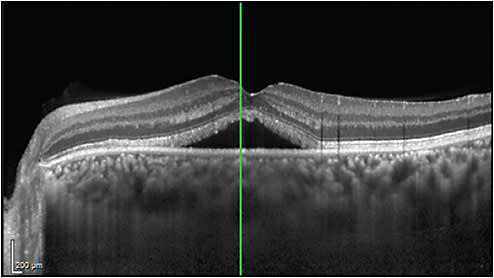

EDI-OCT demonstrated that patients with central serous chorioretinopathy (CSC) have a very thick choroid, which relates to increased choroidal vascular hyperpermeability and hydrostatic pressure changes.6 Enhanced-depth imaging OCT, has also revealed that in all eyes with CSC, besides a thickened subfoveal choroid, there is also a thinning of the inner choroidal layer and an enlargement of the underlying hyporeflective choroidal lumina. In addition, some eyes with CSC may demonstrate a dome-shaped RPE elevation, a double-layer sign of the RPE/Bruch membrane complex, and RPE microrips (Figure 1).7